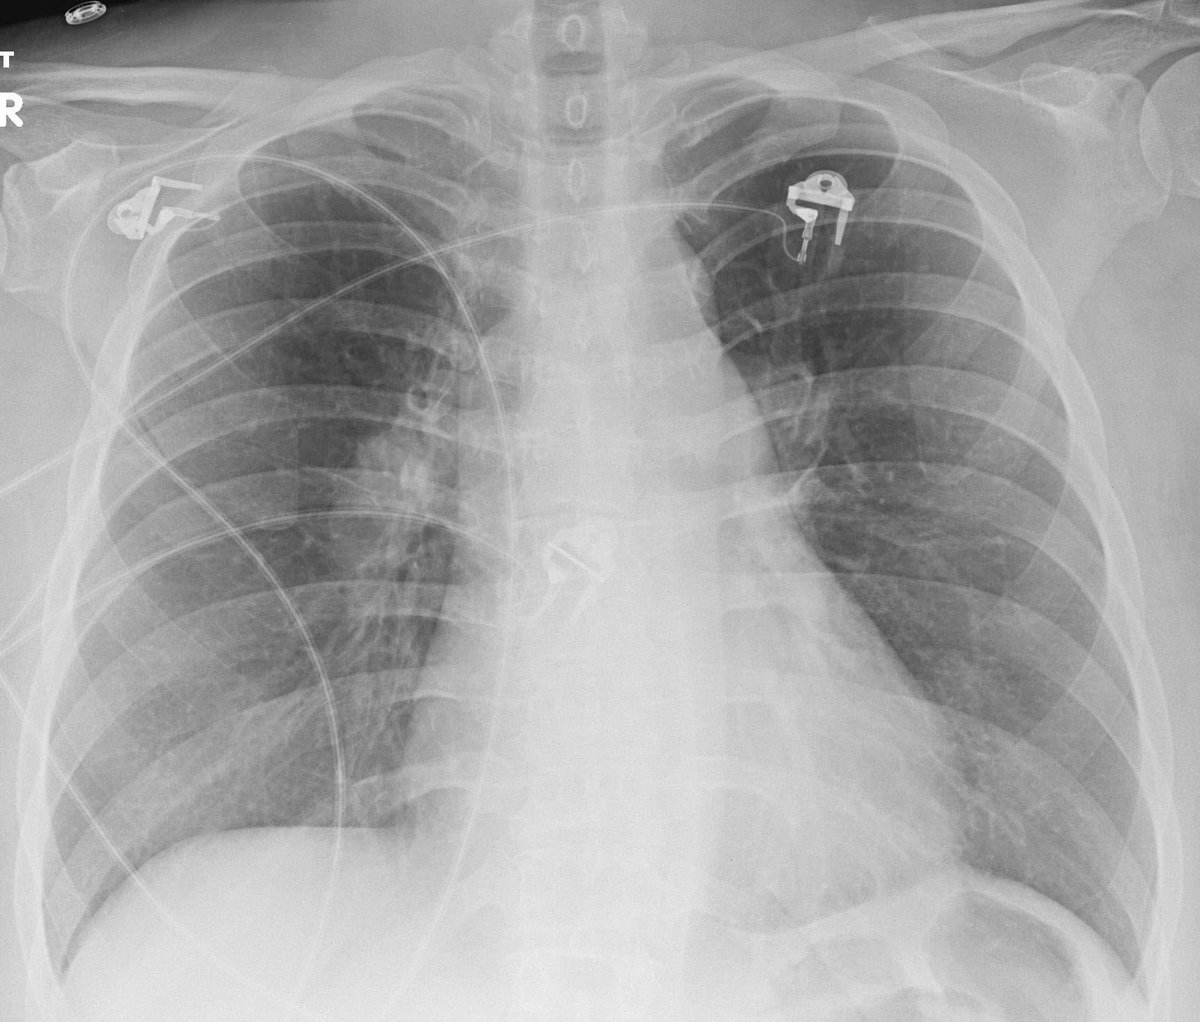

Sign? A. Hampton hump B. Hilum overlay C. Ring around the artery D. Knuckle

#radres#radedu#meded#FOAMed@TanMohammedMD@DarelHeitkamp@StefanTigges Answer: Knuckle. CXR - enlarged proximal R hilum with abrupt tapering; CT - enlarged R pulmonary artery filled with thrombus.pic.twitter.com/UJnJvi8GyZ